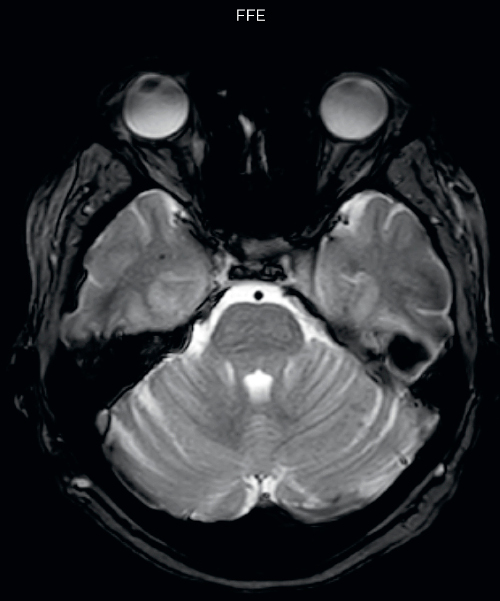

Hemosiderin foci in brain

Gradient echo imaging and SWIp are compared in a patient with radiation-induced foci of hemosiderin deposition. A greater number of small foci is seen on the SWIp image. Ingenia 3.0T

“With SWIp we are basically looking for blood byproducts. It is a sensitive method for visualizing small lesions containing deoxygenated blood. In our comparison, SWIp images are vastly better than gradient echo imaging, there’s no question of that anymore.”

“We find the SWIp images very useful in three areas in particular. In patients with a history of hypertension, it offers clear visualization of hemosiderin deposition from hypertensive hemorrhages. We certainly see a greater number of foci of hemosiderin deposition on the SWIp images than on the T2* gradient echo images. In addition, it also helps us visualize amyloid depositions in patients with amyloid angiopathy.”